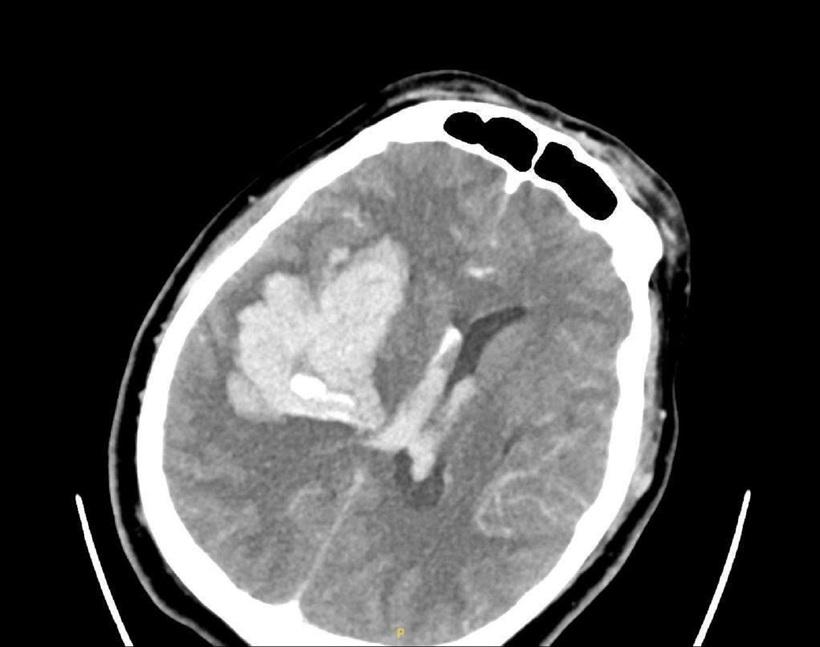

Hình ảnh phim chụp bệnh nhân bị xuất huyết não lượng lớn bán cầu phải. Ảnh: VietNamnet

Tại đây, ảnh chụp CT não cho thấy bệnh nhân bị xuất huyết não lớn, được đặt nội khí quản để bảo vệ đường thở và chuyển mổ cấp cứu.